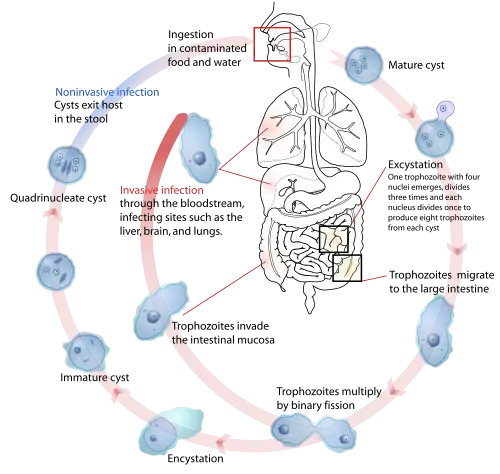

| The life-cycle of various intestinal Entamoeba species | |

Amoebiasis, or amoebic dysentery, is an infection of the intestines caused by a parasitic amoeba Entamoeba histolytica.[4][5] Amoebiasis can be present with no, mild, or severe symptoms.[2] Symptoms may include lethargy, loss of weight, colonic ulcerations, abdominal pain, diarrhea, or bloody diarrhea.[6][2] Complications can include inflammation and ulceration of the colon with tissue death or perforation, which may result in peritonitis.[2] Anemia may develop due to prolonged gastric bleeding.[2]

Cysts of Entamoeba can survive for up to a month in soil or for up to 45 minutes under fingernails.[2] Invasion of the intestinal lining results in bloody diarrhea.[2] If the parasite reaches the bloodstream it can spread through the body, most frequently ending up in the liver where it can cause amoebic liver abscesses.[2] Liver abscesses can occur without previous diarrhea.[2] Diagnosis is made by stool examination using microscopy, but it can be difficult to distinguish E. histolytica from other harmless entamoeba species.[4] An increased white blood cell count may be present in severe cases.[2] The most accurate test is finding specific antibodies in the blood, but it may remain positive following treatment.[2] Bacterial colitis can result in similar symptoms.[2]

Infections can sometimes last for years if there is no treatment. Symptoms, if present, can take anywhere from days to years to develop,[10] but usually it is about two to four weeks.[11] Symptoms can range from mild diarrhea to dysentery with blood, coupled with intense abdominal pains. Extra-intestinal complications might also arise as a result of invasive infection which includes colitis, liver, lung, or brain abscesses.[9] The blood comes from bleeding lesions created by the amoebae invading the lining of the colon. In about 10% of invasive cases the amoebae enter the bloodstream and may travel to other organs in the body. Most commonly this means the liver,[12] as this is where blood from the intestine reaches first, but they can end up almost anywhere in the body.

The ingestion of one viable cyst may cause an infection.[14]

Transmission

Amoebiasis is usually transmitted by the fecal-oral route,[9] but it can also be transmitted indirectly through contact with dirty hands or objects as well as by anal-oral contact. Infection is spread through ingestion of the cyst form of the parasite, a semi-dormant and hardy structure found in feces. Any non-encysted amoebae, or trophozoites, die quickly after leaving the body but may also be present in stool: these are rarely the source of new infections.[9] Since amoebiasis is transmitted through contaminated food and water, it is often endemic in regions of the world with limited modern sanitation systems, including México, Central America, western South America, South Asia, and western and southern Africa.[16]